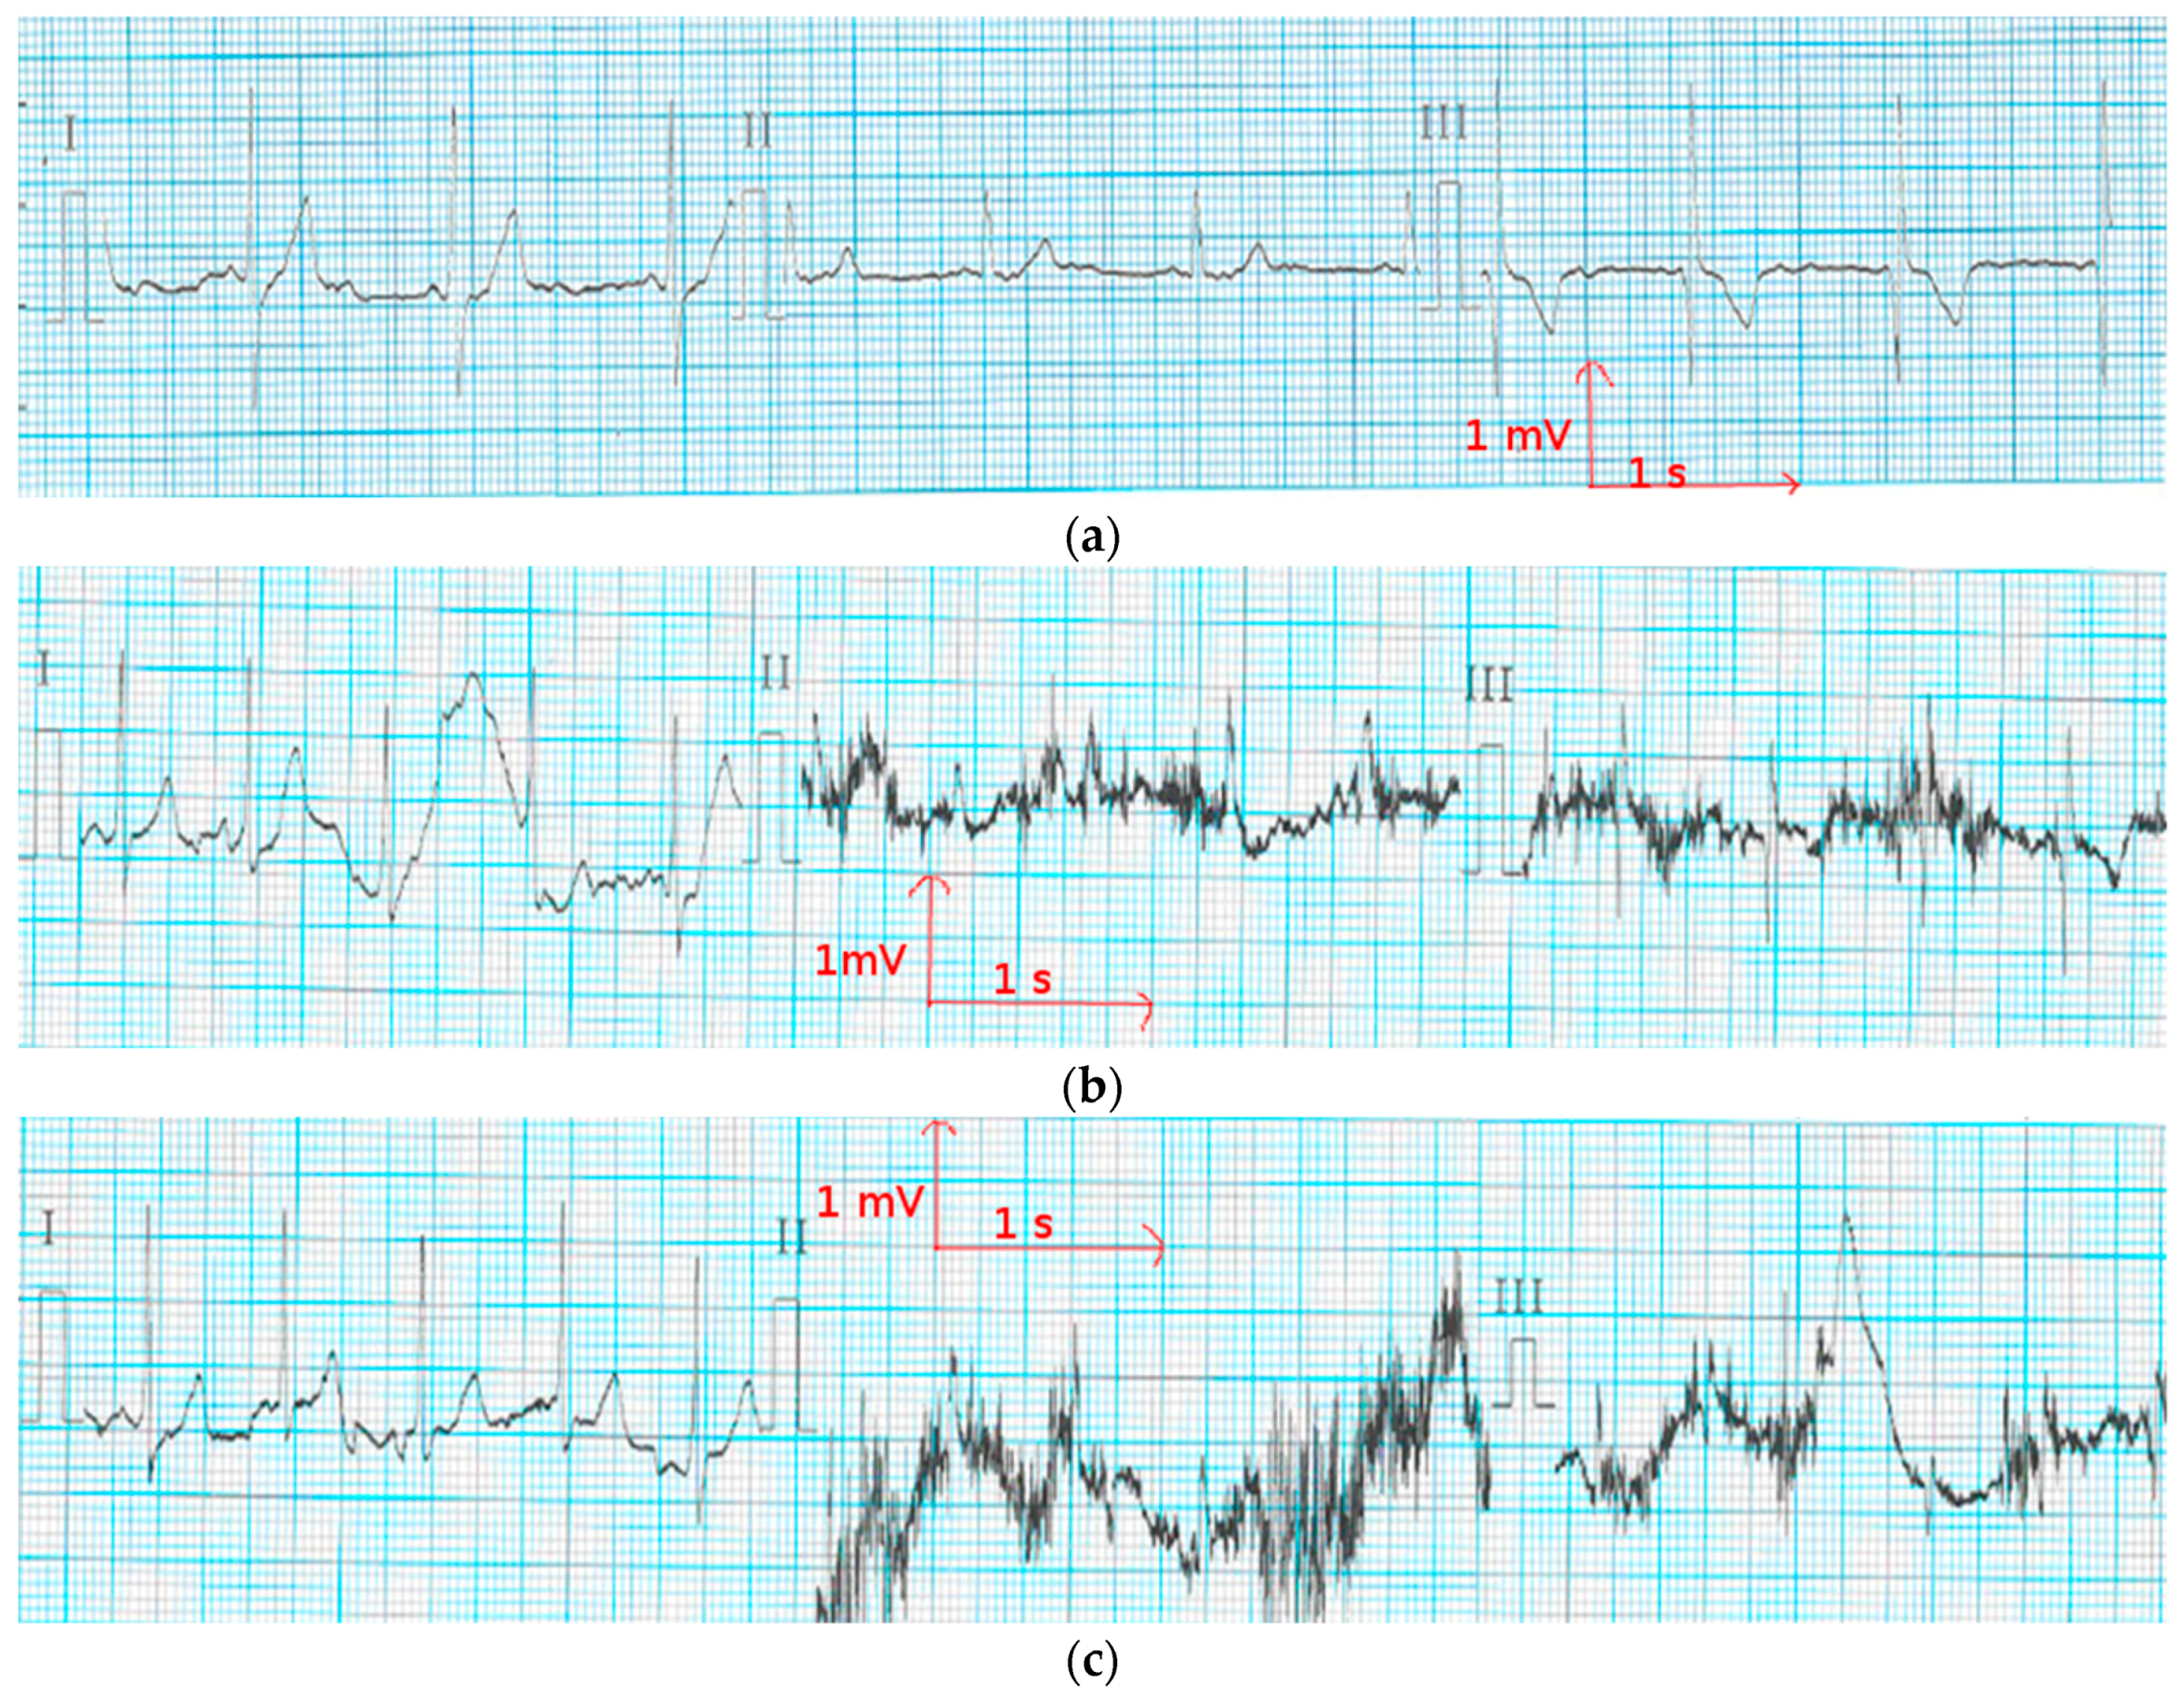

3.3. Evaluation of Textile Electrodes in ECG Monitoring